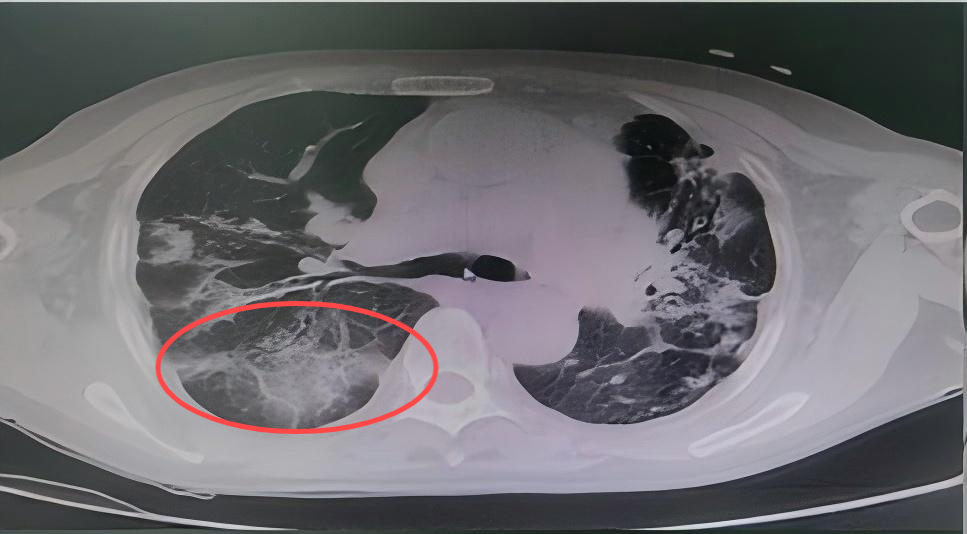

患者郑某某,因支气管扩张、空洞反复咯血十余年,再次复发后,咯血量明显增多,在当地治疗一周因效果不佳转入我院,就诊于急诊时仍咯血200ml,呼吸与危重症医学科立即启动绿色通道将患者送入介入室手术,术中仍持续咯血,在实施支气管动脉栓塞术后,患者咯血立即停止。在呼吸与危重症医学科医护人员的精心治疗下,患者最终好转出院,至今无复发。

CT提示患者双肺大片病灶,支气管扩张,空洞。

病 灶

空 洞

支气管扩张